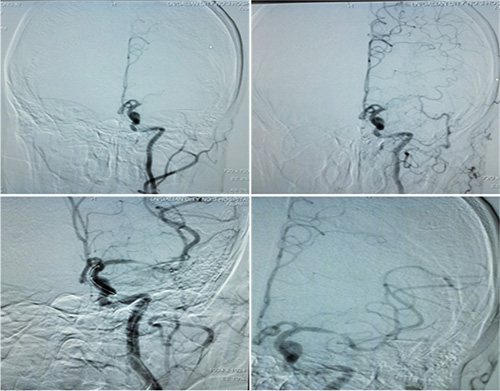

“時間窗和組織窗該相信誰?”經(jīng)驗豐富的張靜波主任對該患者進行及時的CT灌注成像檢查,結(jié)果顯示灌注缺血區(qū)與核心梗死的不匹配,意味著患者還有可以挽救的腦組織,值得進行介入取栓治療。取栓后,患者腦血管實現(xiàn)完全再通。

這位患者入院時NIHSS(注:美國國立衛(wèi)生研究院卒中量表,分值越高表明卒中越嚴重)評分為18分。經(jīng)過及時治療,患者術(shù)后NIHSS分值降至4分,基本能實現(xiàn)生活自理。

▲取栓前后對比圖:患者腦血管實現(xiàn)再通